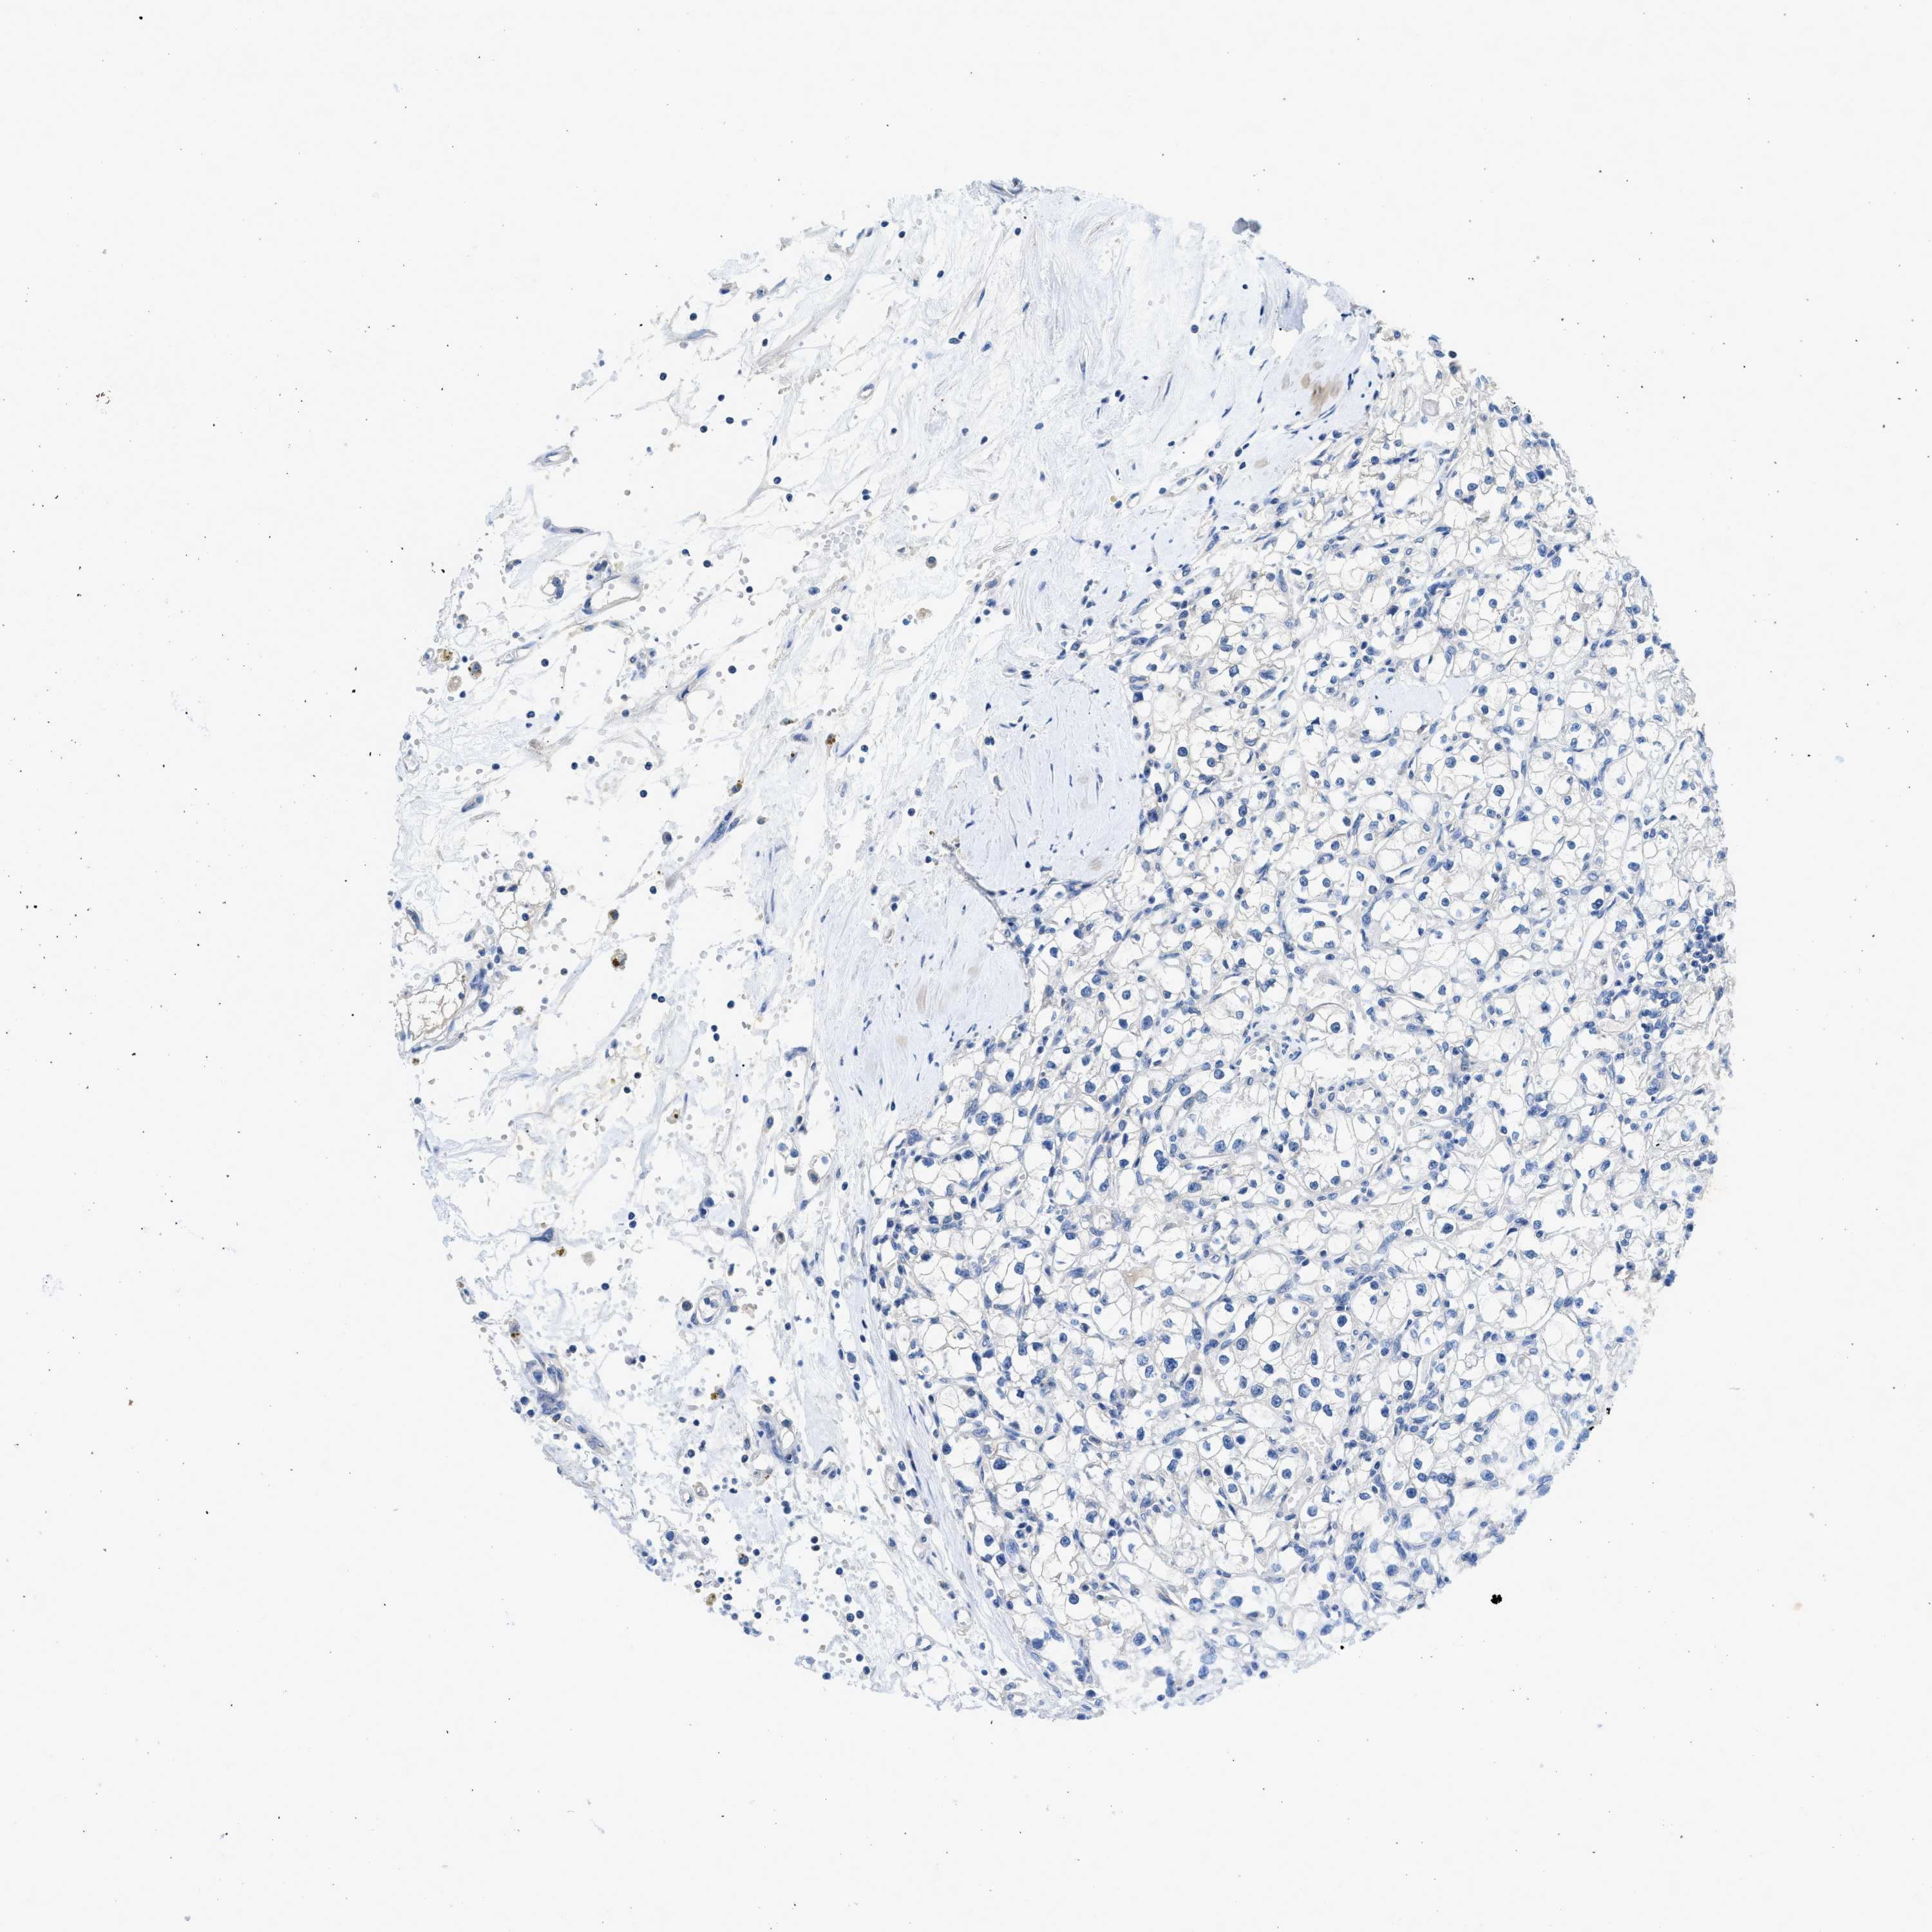

KIDNEY RENAL CLEAR CELL CARCINOMA (VALIDATION) - Interactive survival scatter ploti

The Survival Scatter plot shows the clinical status (i.e. dead or alive) for all individuals in the patient cohort, based on the same data that underlies the corresponding Kaplan-Meier plots. Patients that are alive at last time for follow-up are shown in blue and patients who have died during the study are shown in red.

The x-axis shows the expression levels (FPKM) of the investigated gene in the tumor tissue at the time of diagnosis. The y-axis shows the follow-up time after diagnosis (years). Both axes are complimented with kernel density curves demonstrating the data density over the axes. The top density plot shows the expression levels (FPKM) distribution among dead (red) and alive patients (blue). The right density plot shows the data density of the survived years of dead patients with high and low expression levels respectively, stratified using the cutoff indicated by the vertical dashed line through the Survival Scatter plot. This cutoff is automatically defined based on the FPKM cutoff that minimizes the p-score. The cutoff can be changed by dragging the vertical line or by entering a cutoff value in the square labeled "Current cut-off".

Under the Survival Scatter plot the p-score landscape (black curve; left axis) is shown together with dead median separation (red curve; right axis). Dead median separation is the difference in median mRNA expression between patients who have died with high and low expression, respectively. It is calculated as follows: median FPKM expression of dead patients with high expression - median FPKM expression of dead patients with low expression. This is intended to aid the user in visually exploring custom cutoffs and the associated p-scores and dead median separation.

Individual patient data is displayed and can be filtered by clicking on one or more of the category buttons on the top of the page. Categories describing expression level and patient information include: high, low, alive, dead, female, male and tumor stages. The scale of the x-axis can be toggled between linear and log-scale by clicking on the "x log" button. Mouse-over function shows TCGA ID, patient information and mRNA expression (FPKM) for each patient.

& Survival analysisi

Kaplan-Meier plots summarize results from analysis of correlation between mRNA expression level and patient survival. Patients were divided based on level of expression into one of the two groups "low" (under cut off) or "high" (over cut off). X-axis shows time for survival (years) and y-axis shows the probability of survival, where 1.0 corresponds to 100 percent.

SLC10A6 is validated prognostic, high expression is favorable in Kidney Renal Clear Cell Carcinoma (validation)

: 1.34

Average pTPM 1.6

Number of samples 100